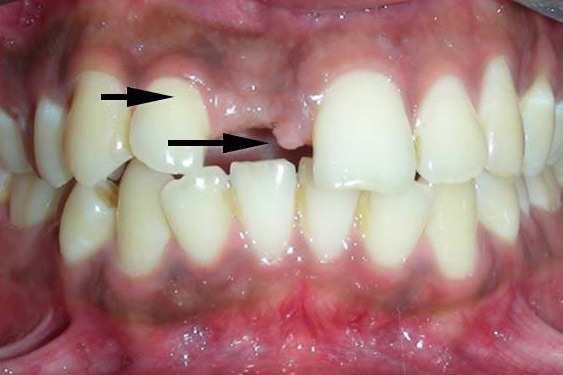

| Severe forwardness of teeth required correction with removal of 3 premolars. |

| The second incisor was brought in place of the first the canine was brought in place of the second incisor |

| And that’s how we ended with his treatment. |